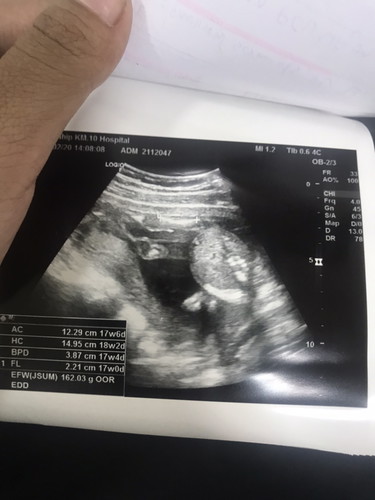

17+6weeks

เเม่ๆคะวันนี้น้องไปอัลตร้าซาวด์มาเเต่มาดดูรูปแสกน มองยังไงก็มองไม่ออกตรงไหนเป็นอะไร อีกอย่างหมอก็ไม่ได้บอกเพศด้วย เเม่ๆคิดยังไงกันคะ กำหนดคลอด19 ก.ค ค่ะ อยากรู้เพศเเล้วเเต่หมอไม่เเจ้งอะไรเลย